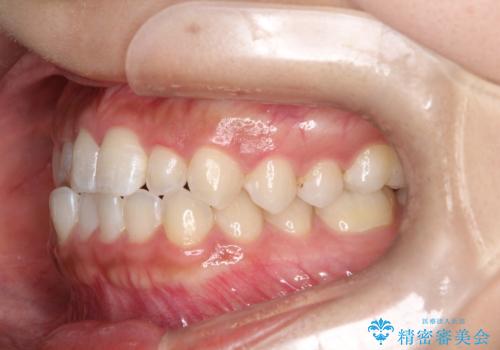

- 前歯の凸凹を主訴に来院された患者様です。

カウンセリング時に、側切歯が矮小歯であることを指摘したところ、適切な幅径での修復を希望されました。

インビザラインを用い、計画通りに歯並びを改善することができました。

矮小歯の幅径を大きくすることで、より理想的な噛み合わせを作ることができます。